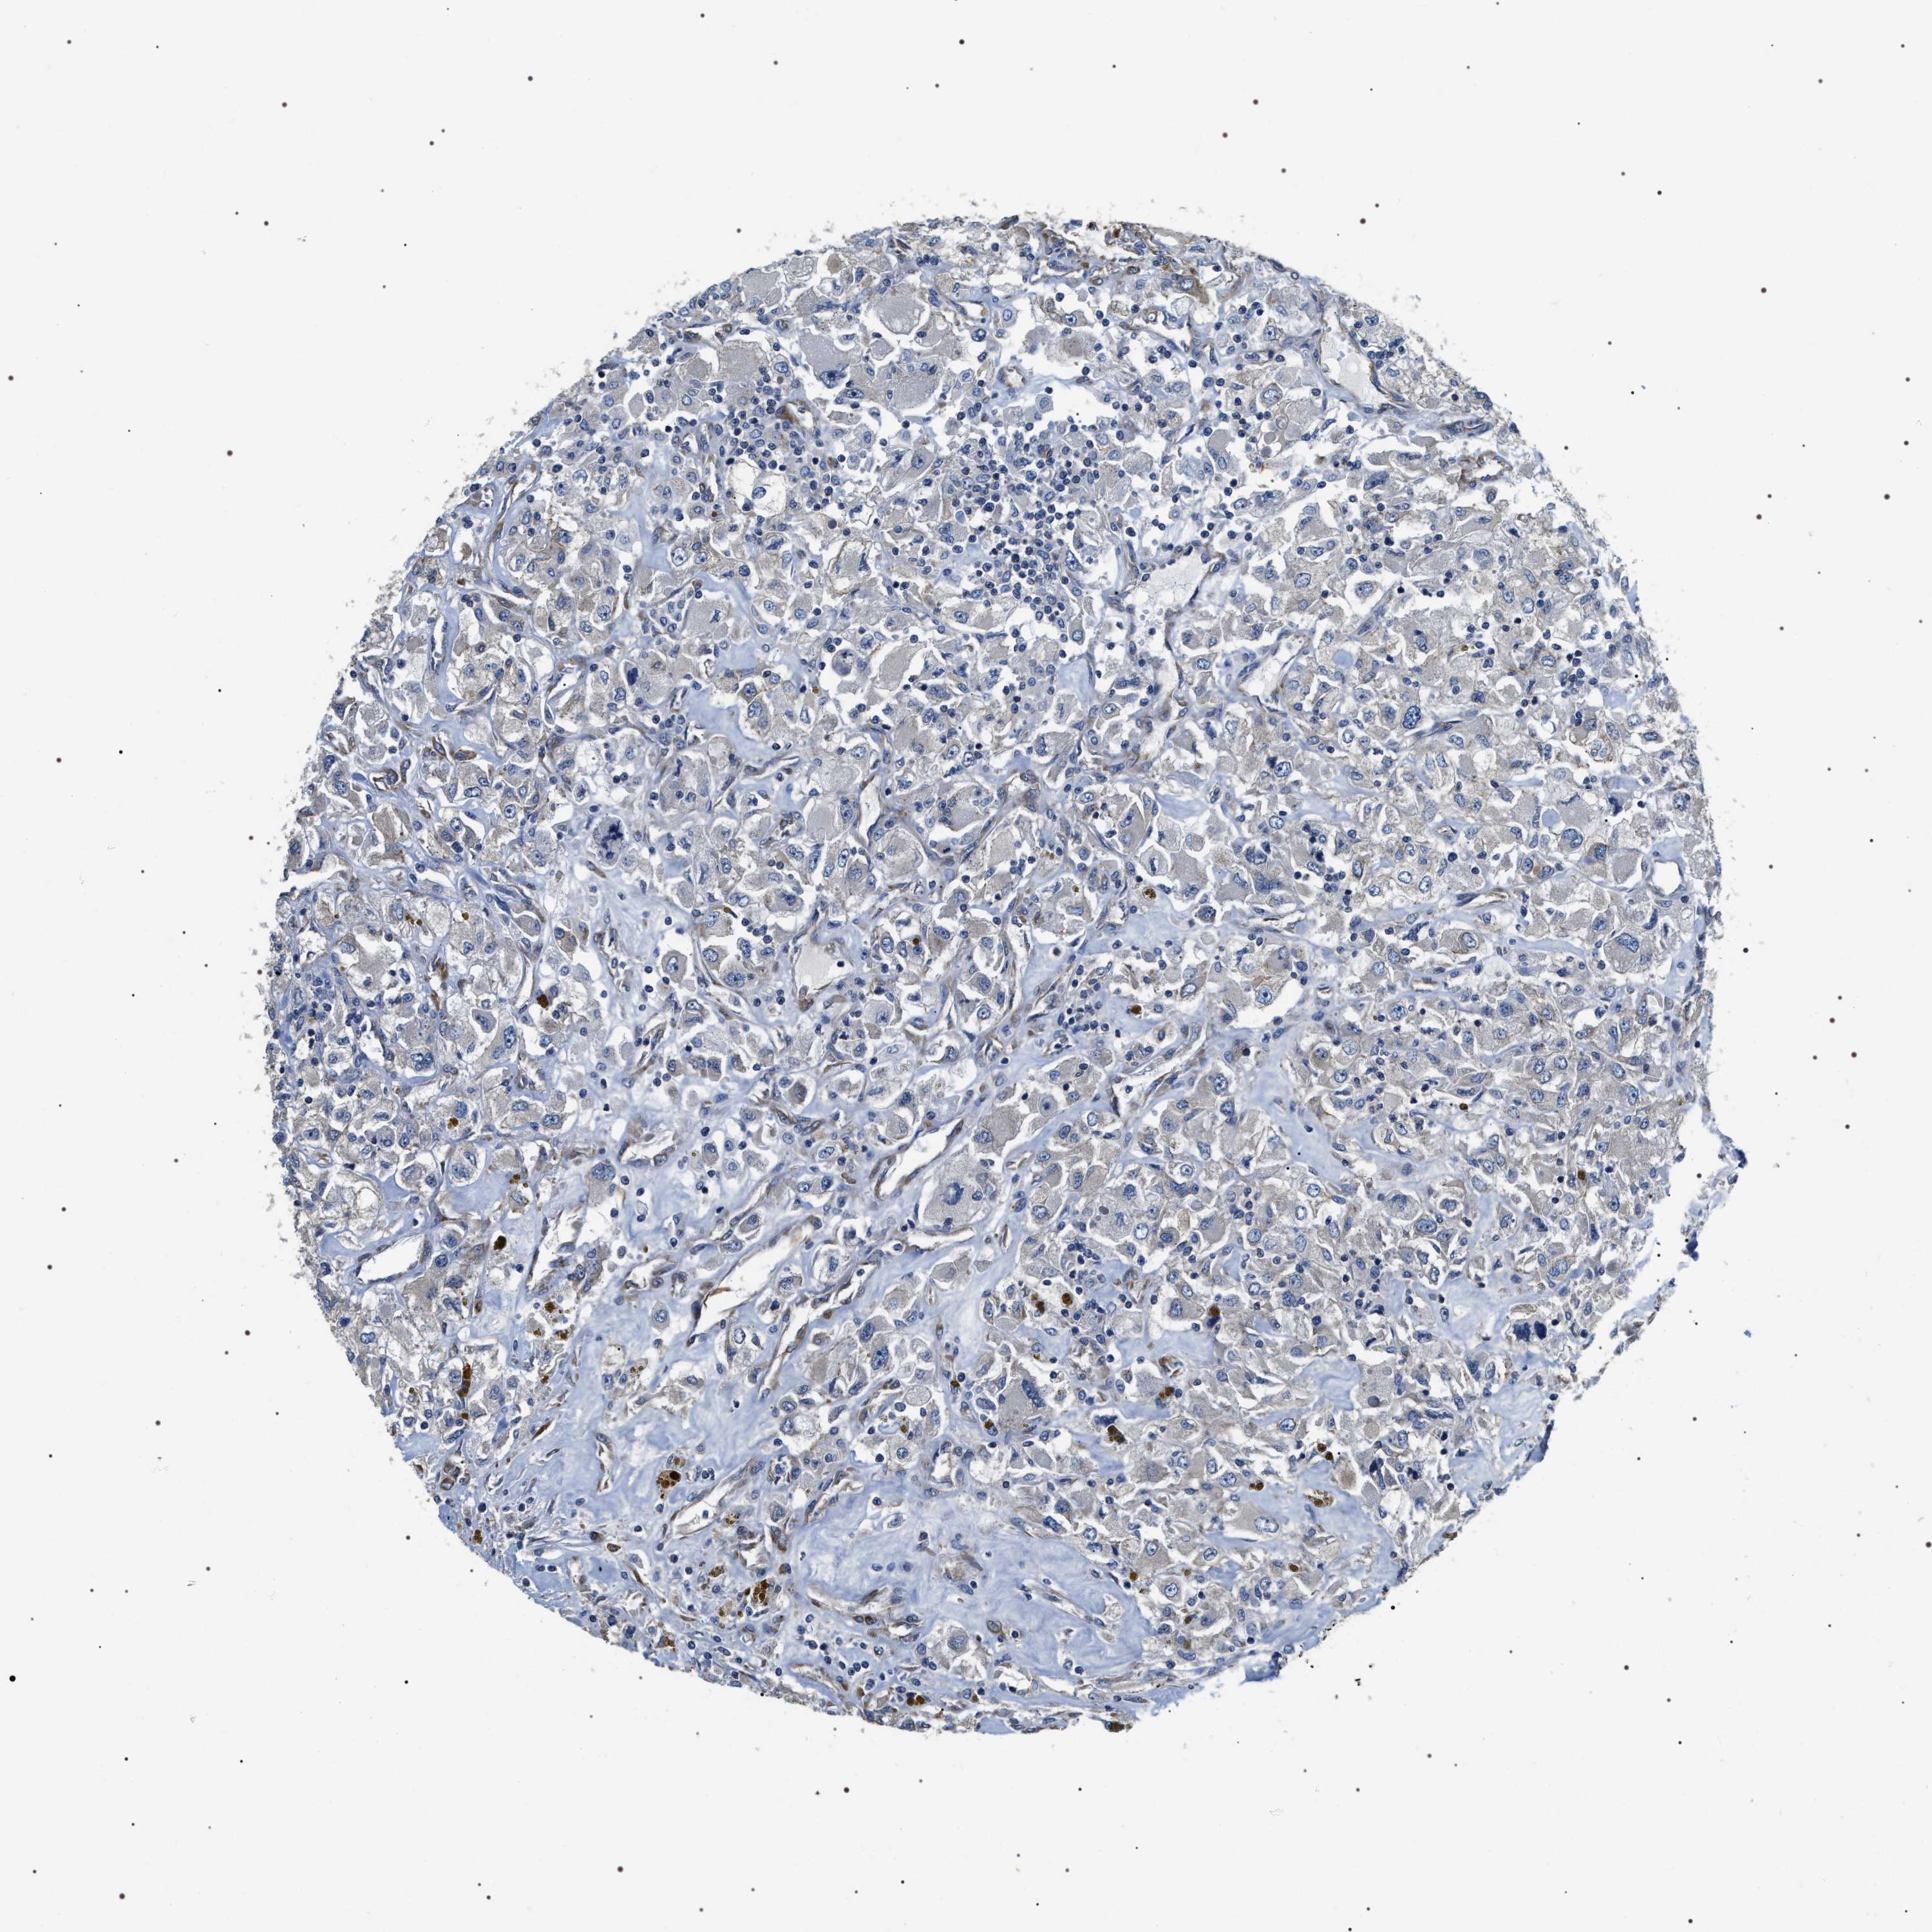

KIDNEY RENAL CLEAR CELL CARCINOMA (TCGA) - Interactive survival scatter ploti

The Survival Scatter plot shows the clinical status (i.e. dead or alive) for all individuals in the patient cohort, based on the same data that underlies the corresponding Kaplan-Meier plots. Patients that are alive at last time for follow-up are shown in blue and patients who have died during the study are shown in red.

The x-axis shows the expression levels (FPKM) of the investigated gene in the tumor tissue at the time of diagnosis. The y-axis shows the follow-up time after diagnosis (years). Both axes are complimented with kernel density curves demonstrating the data density over the axes. The top density plot shows the expression levels (FPKM) distribution among dead (red) and alive patients (blue). The right density plot shows the data density of the survived years of dead patients with high and low expression levels respectively, stratified using the cutoff indicated by the vertical dashed line through the Survival Scatter plot. This cutoff is automatically defined based on the FPKM cutoff that minimizes the p-score. The cutoff can be changed by dragging the vertical line or by entering a cutoff value in the square labeled "Current cut-off".

Under the Survival Scatter plot the p-score landscape (black curve; left axis) is shown together with dead median separation (red curve; right axis). Dead median separation is the difference in median mRNA expression between patients who have died with high and low expression, respectively. It is calculated as follows: median FPKM expression of dead patients with high expression - median FPKM expression of dead patients with low expression. This is intended to aid the user in visually exploring custom cutoffs and the associated p-scores and dead median separation.

Individual patient data is displayed and can be filtered by clicking on one or more of the category buttons on the top of the page. Categories describing expression level and patient information include: high, low, alive, dead, female, male and tumor stages. The scale of the x-axis can be toggled between linear and log-scale by clicking on the "x log" button. Mouse-over function shows TCGA ID, patient information and mRNA expression (FPKM) for each patient.

& Survival analysisi

Kaplan-Meier plots summarize results from analysis of correlation between mRNA expression level and patient survival. Patients were divided based on level of expression into one of the two groups "low" (under cut off) or "high" (over cut off). X-axis shows time for survival (years) and y-axis shows the probability of survival, where 1.0 corresponds to 100 percent.

ZC3HAV1L is not prognostic in Kidney Renal Clear Cell Carcinoma (TCGA)

: 9.88

Average pTPM 7.1

Number of samples 521